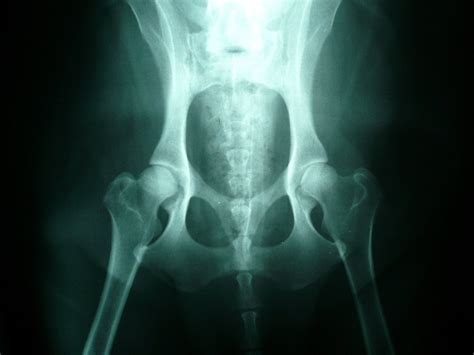

Naša ortopedická služba ponúka rozsiahly repertoár diagnostických metód a terapií zameraných na zdravie kostí a pohybového aparátu vášho zvieraťa. Naši špecialisti sa venujú starostlivosti o kosti a pohybový aparát vášho miláčika. Veterinárna klinika Vinohrady Nové Zámky ponúka transparentný cenník služieb. Môžete sa spoľahnúť, vášmu miláčikovi poskytneme kvalifikovanú odbornú pomoc. Využite konzultačnú, klinickú a poradenskú skúsenosť na základe 46 ročných činností v oblasti veterinárnej medicíny - zvlášť v ortopédii, röntgenológii a chirurgii psov a mačiek a tiež chirurgickej a ortopedickej onkológii na Univerzite veterinárskeho lekárstva a farmácie.

- Dysplázia bedrových a lakťových kĺbov - geneticky podmienené vývojové ochorenie.